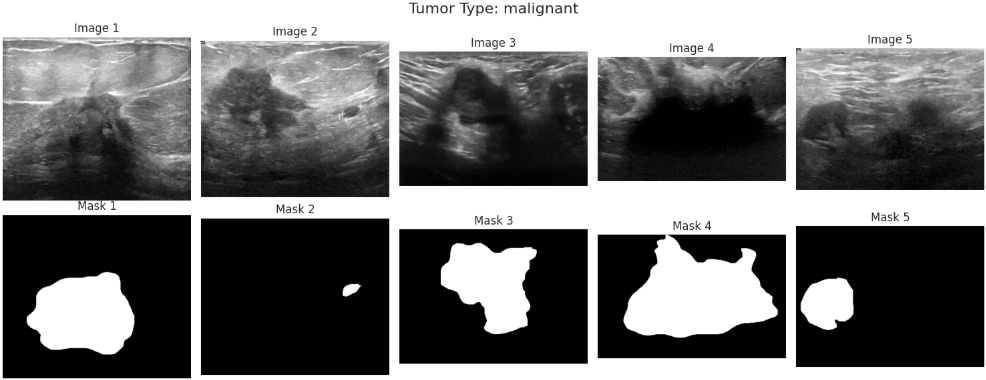

在了解数据集的类别分布之后,还需要进一步观察具体图像样本及其对应的标注信息。乳腺超声数据集中不仅包含原始图像,还提供了对应的病灶掩膜(mask),这些掩膜标注能够指示病灶区域的位置,对于后续模型学习病变区域特征具有重要意义。因此,通过随机抽取不同类别样本并同时展示原始图像与对应掩膜,可以直观了解数据质量以及标注的准确性,从而为后续模型设计和训练提供更加清晰的参考。

import matplotlib.pyplot as plt

for tumor in tumor_types:

# 从当前类别中随机抽取若干样本

subset = df[df['tumor_type'] == tumor].sample(

n=min(n_samples, len(df[df['tumor_type'] == tumor])),

random_state=42

)

# 创建绘图画布,两行分别显示原始图像和对应的mask

fig, axs = plt.subplots(2, n_samples, figsize=(3 * n_samples, 6))

# 设置整体标题

fig.suptitle(f"Tumor Type: {tumor}", fontsize=16)

# 遍历样本进行可视化

for i, (idx, row) in enumerate(subset.iterrows()):

# 读取原始超声图像(灰度模式)

image = cv2.imread(row['image_path'], cv2.IMREAD_GRAYSCALE)

# 读取对应的病灶掩膜图像

mask = cv2.imread(row['mask_path'], cv2.IMREAD_GRAYSCALE)

# 显示原始图像

axs[0, i].imshow(image, cmap='gray')

axs[0, i].axis('off')

axs[0, i].set_title(f"Image {i+1}")

# 显示对应的掩膜图像

axs[1, i].imshow(mask, cmap='gray')

axs[1, i].axis('off')

axs[1, i].set_title(f"Mask {i+1}")

# 调整子图布局

plt.tight_layout()

# 显示图像

plt.show()